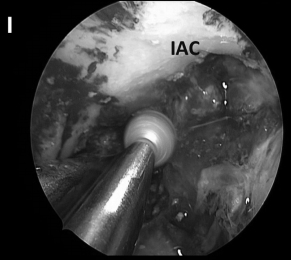

▼(I)s使用磨钻去除该区域粘附于岩骨的病变包膜,但切除岩骨深处病变的增强部分考虑是不安全的,因为它与内听神经关系密切。

▼(J)使用 Endocameleon 内镜仔细检查术野、鼻道(IAC)